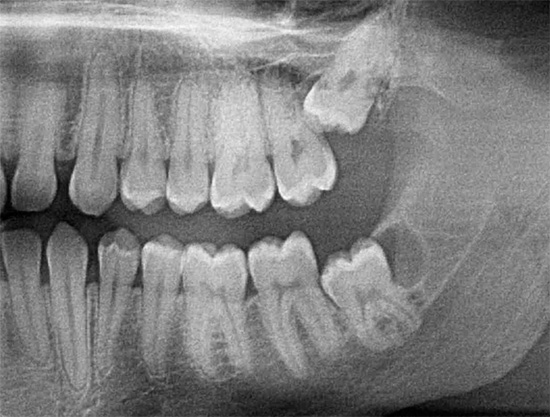

Como o dente do siso costuma ter uma localização não padrão e um grande número de raízes, um raio-X é sempre realizado antes da remoção complexa. Muitos cirurgiões-dentistas não realizam a remoção de um dente do siso sem uma imagem, exceto nas situações mais emergenciais ou quando não é possível fazê-lo imediatamente por várias razões.

A natureza da complexidade da intervenção é determinada pelo cirurgião-dentista em uma instituição especializada e, como observado acima, a remoção nunca começa sem um raio-X. A complexidade de sua remoção depende da natureza da localização do dente no orifício. Se o dente estiver localizado completamente no osso e quase estiver ao longo da mandíbula, a operação poderá demorar muito tempo, à medida que as gengivas forem excisadas, o osso será cortado com a separação da coroa e das raízes dos dentes, seguido de uma extração em fases do orifício ósseo.